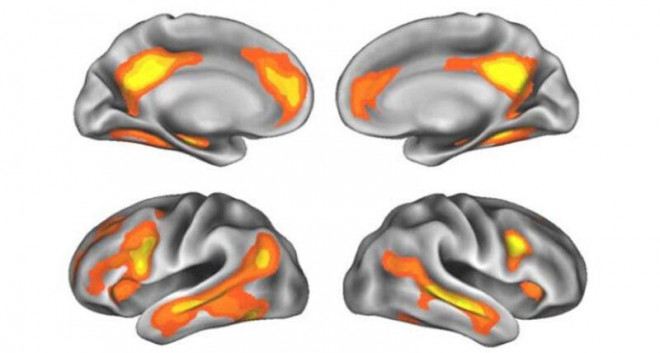

Jacobs và các đồng nghiệp của bà đã phát hiện ra rằng các vùng não phát triển và co lại trong suốt nhiều ngày, những thay đổi liên quan đến nồng độ hormone trong chu kỳ kinh nguyệt. Sự thay đổi này được tìm thấy ở vùng hồi hải mã, một cấu trúc não gắn liền với học tập và trí nhớ, và các khu vực lân cận.

Tương tự, mang thai và sự thay đổi hormone sau đó cũng có thể thay đổi não bộ. Quá trình này dường như là giai đoạn trưởng thành thứ hai của não bộ, giống như quá trình sàng lọc xảy ra ở tuổi vị thành niên.

Một nghiên cứu từ năm 2016 cho thấy: Mang thai đi kèm với sự giảm sút một số bộ phận trong não của người mẹ (các khu vực màu đỏ và vàng được đánh dấu trên bốn góc nhìn khác nhau của não bộ).